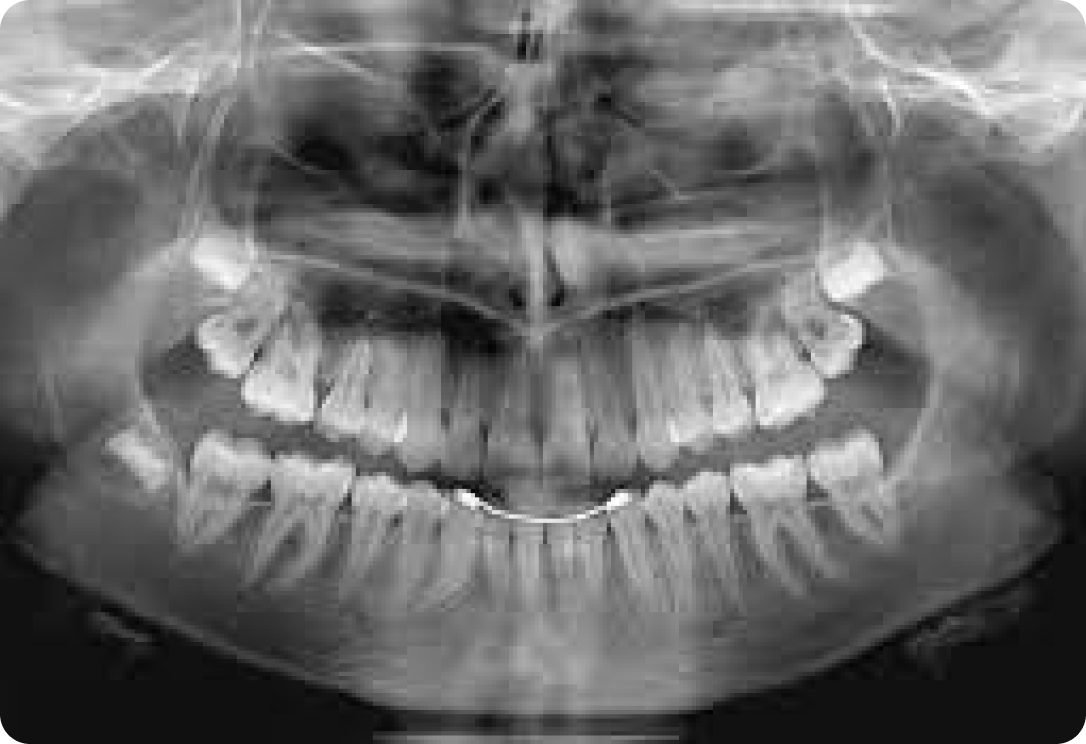

Зачем нужен панорамный снимок зубов